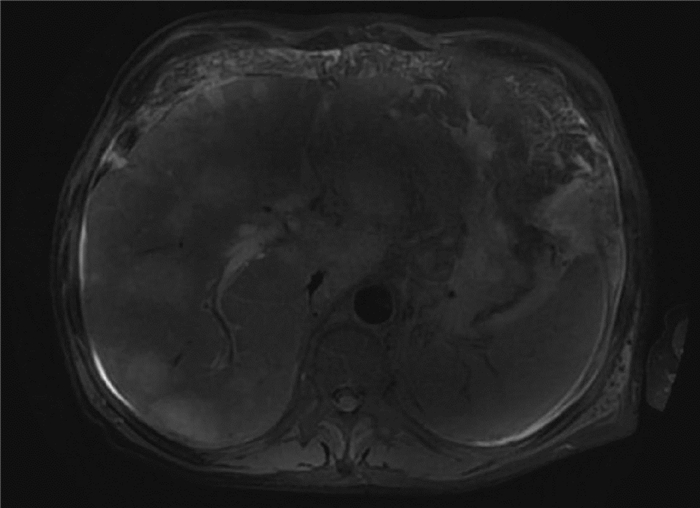

Tuberculous polyserositis after liver transplantation: A case report

Abstract(935) HTML (281) PDF (2200KB)(61)

Abstract: